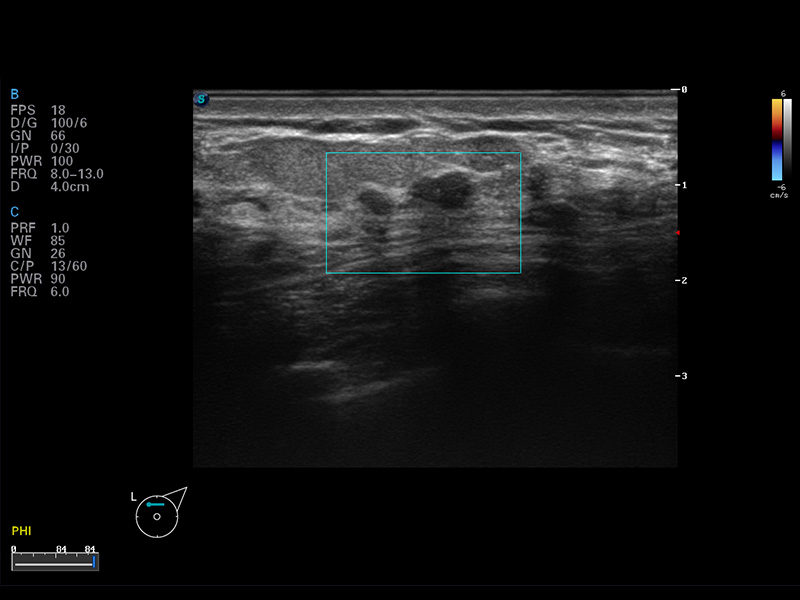

S8 EXP便携式彩色多普勒超声诊断仪是百老汇电子游戏官网研发的高端全身应用型便携彩超。高通道的VIS平台融合可视化(Visual)、智能化(Intelligent)和人性化(Smart)的特点,配以百老汇电子游戏官网自主研发生产的探头大家族,使您能够快速、准确的获得病人信息,提高工作效率的同时减轻疲劳。

μ-Scan微米成像

空间复合成像

3D/4D成像